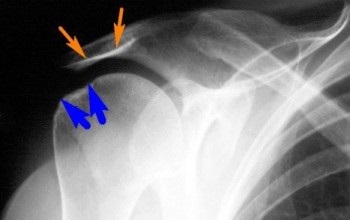

lamă excrescență Nadplechevoy (acromion)

Deformarea brâul umărului, umflarea apare, sangerare este prezent.

Partea exterioară a subclavicular funcției fosa netezită a membrelor superioare este rupt.

Palparea dezvăluie o durere ascuțită la înălțimea de deformare.

Destul de des poate fi detectat sub capătul de piele al fragmentului central de servire fragmente crepitations.

Entorse, fracturi, spre deosebire de procesul nadplechevogo, sub piele marginea rotunjită palpabilă nadplechevogo capăt al claviculă și simptom pozitiv de taste disponibile, care nu se întâmplă niciodată la sfârșitul clavicula fracturi nadplechevogo.

studiu cu raze X clarifică diagnosticul.